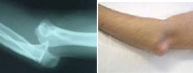

Luxaciones del codo

La articulación del codo tiene lugar entre el húmero y el cúbito y radio. La luxación de codo tiene lugar con mayor frecuencia en la segunda década de la vida. La separación traumática entre brazo y antebrazo es frecuente en el ámbito deportivo, especialmente en aquellos deportes que pueden provocar impactos sobre la mano con el codo en extensión. Ello es posible en artes marciales, futbol, baloncesto y escalada, entre otros.

Esta lesión no sólo compromete las estructuras óseas sino las ligamentosas y neurovasculares por lo que se requiere un meticuloso estudio en el servicio de urgencias para diagnosticar el grado de afectación tratándolo entonces adecuadamente.

En un primer momento la recolocación del codo en situación anatómica es primordial a través de un suave gesto y en algunas ocasiones bajo anestesia. Si a pesar de la congruencia articular, el codo se presenta inestable, puede ser necesario reforzar la estabilidad ósea con una intervención quirúrgica.